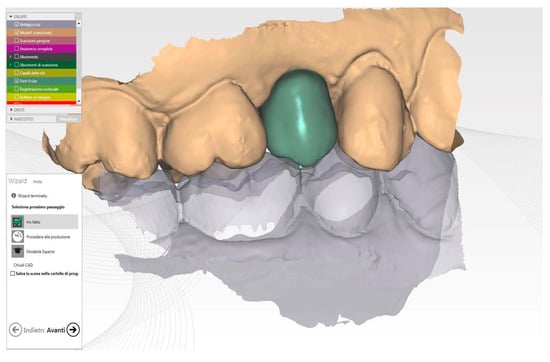

Figure 8.

STL image of final crown Cad modelling.

Using the same software, the final crown was designed, matching the unaltered pre-operative impression, the mucosal tunnel impression, and the provisional impression. The monolithic zirconia crown (Figure 8) (Zirconium BionX2, Zfx, Dachau, Germany) was milled, stained, and sintered (AUSTROMAT 674i, Dekema Dental Keramiköfen GmbH, Freilassing, Germany).